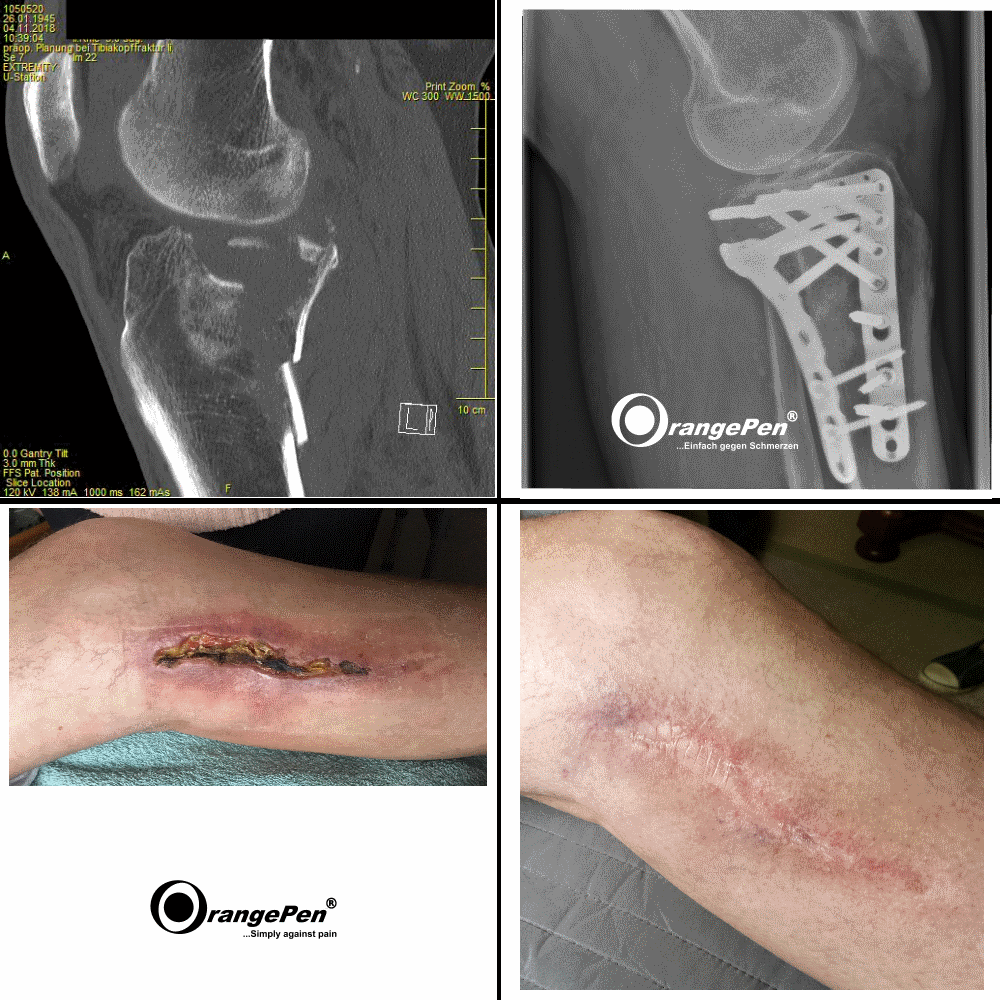

Metal Implants

Metal Implants treated with OrangePen®

For the OrangePen it is of secondary importance whether there is metal in the body. Only the treatment time must be adapted to the new requirements. Even pacemaker patients have been treated successfully.